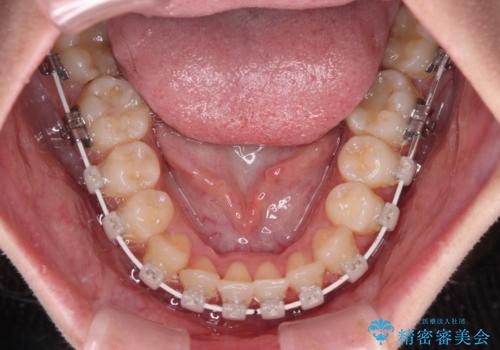

- 審美装置

- 1年1ヶ月

- 10-30回

インビザラインなどのマウスピース矯正は、楽に治療できると思われている方もいらっしゃると思いますが、毎日ストイックに22時間の装着を続けていくことは、決して楽なことではありません。

楽して治療したい方には、ワイヤー矯正がお勧めです。